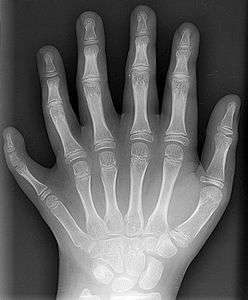

Some mutations occur in "toolkit" or regulatory genes. Changes in these often have large effects on the phenotype of the individual because they regulate the function of many other genes. Most, but not all, mutations in regulatory genes result in non-viable embryos. Some nonlethal regulatory mutations occur in HOX genes in humans, which can result in a cervical rib[83] or polydactyly, an increase in the number of fingers or toes.[84] When such mutations result in a higher fitness, natural selection favours these phenotypes and the novel trait spreads in the population. Established traits are not immutable; traits that have high fitness in one environmental context may be much less fit if environmental conditions change. In the absence of natural selection to preserve such a trait, it becomes more variable and deteriorate over time, possibly resulting in a vestigial manifestation of the trait, also called evolutionary baggage. In many circumstances, the apparently vestigial structure may retain a limited functionality, or may be co-opted for other advantageous traits in a phenomenon known as preadaptation. A famous example of a vestigial structure, the eye of the blind mole-rat, is believed to retain function in photoperiod perception.[85]